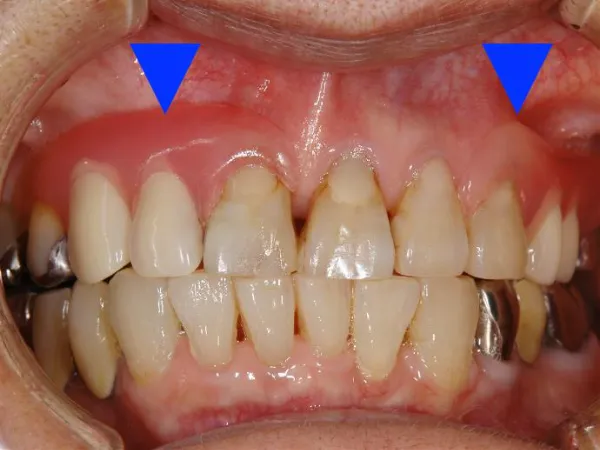

歯の上下や水平な位置関係を確認しながら咬み合わせを調整します。

患者様に快適に使って頂けるように、歯並びや歯の見え方、口の周りのふくらみの様子などをできるだけ細かく確認します。出来上がりの状態に歪みや変形がないかを確認して、最終的に各患者様に合った入れ歯となるよう調整します。